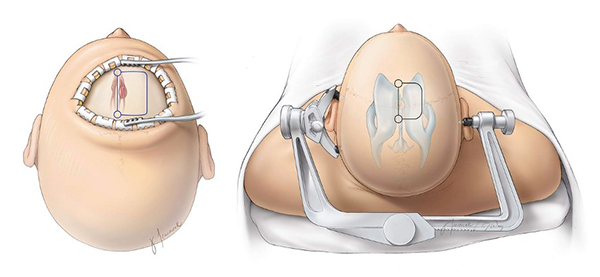

Paciente en decúbito dorsal, fijación con cabezal de Mayfield en posición neutra con ligera flexión y elevación de la cabeza respecto al tórax, rotación aproximada de 15° para que por gravedad separe al hemisferio derecho. Planificación con neuronavegador (sistema BrainLab Curve) utilizando IRM en secuencias T1 y T2 para definir estructuras vasculares importantes, en este caso el seno longitudinal superior (SSS) y arterias cerebrales anteriores con sus ramas pericallosas y calloso marginal, así como vascularización del tumor, que están presentes en el abordaje quirúrgico. Diéresis en herradura, incidiendo por planos logrando exposición ósea hasta identificar la sutura coronal y sagital. Craneotomía practicada en forma de herradura, situándose ⅔ delante y ⅓ detrás de la sutura coronal sobrepasando al menos 1 cm la línea media para exponer y desplazar al SSS y lograr una mejor exposición de la fisura interhemisférica (Figura 3).

Figura 3. Posicionamiento, fijación, diéresis y craneotomía para abordaje ITcA. (Illustración de J. Travnicek cortesía de: The Neurosurgical Atlaspor Aaron Cohen-Gadol, MD)